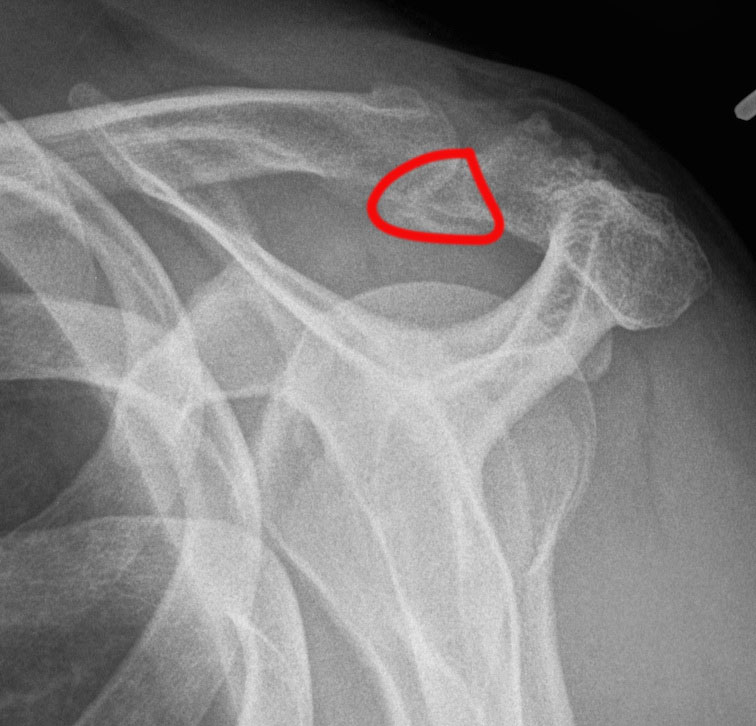

X-ray

Best seen on axillary lateral

Factors favoring diagnosis of os acromiale over fracture

- bilateral occurrence (xray other side)

- rounded borders with uniform space

Axillary lateral showing meso-acromion Scapula lateral xray showing os acromiale